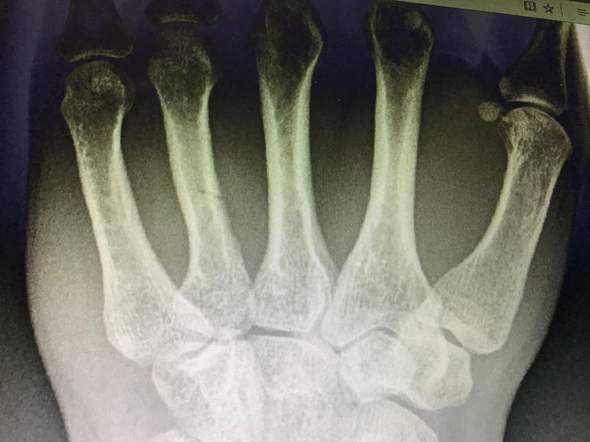

Mittelhandknochenbruch

Mittelhandknochenbruch Heilung Ohne Op Hand Fraktur